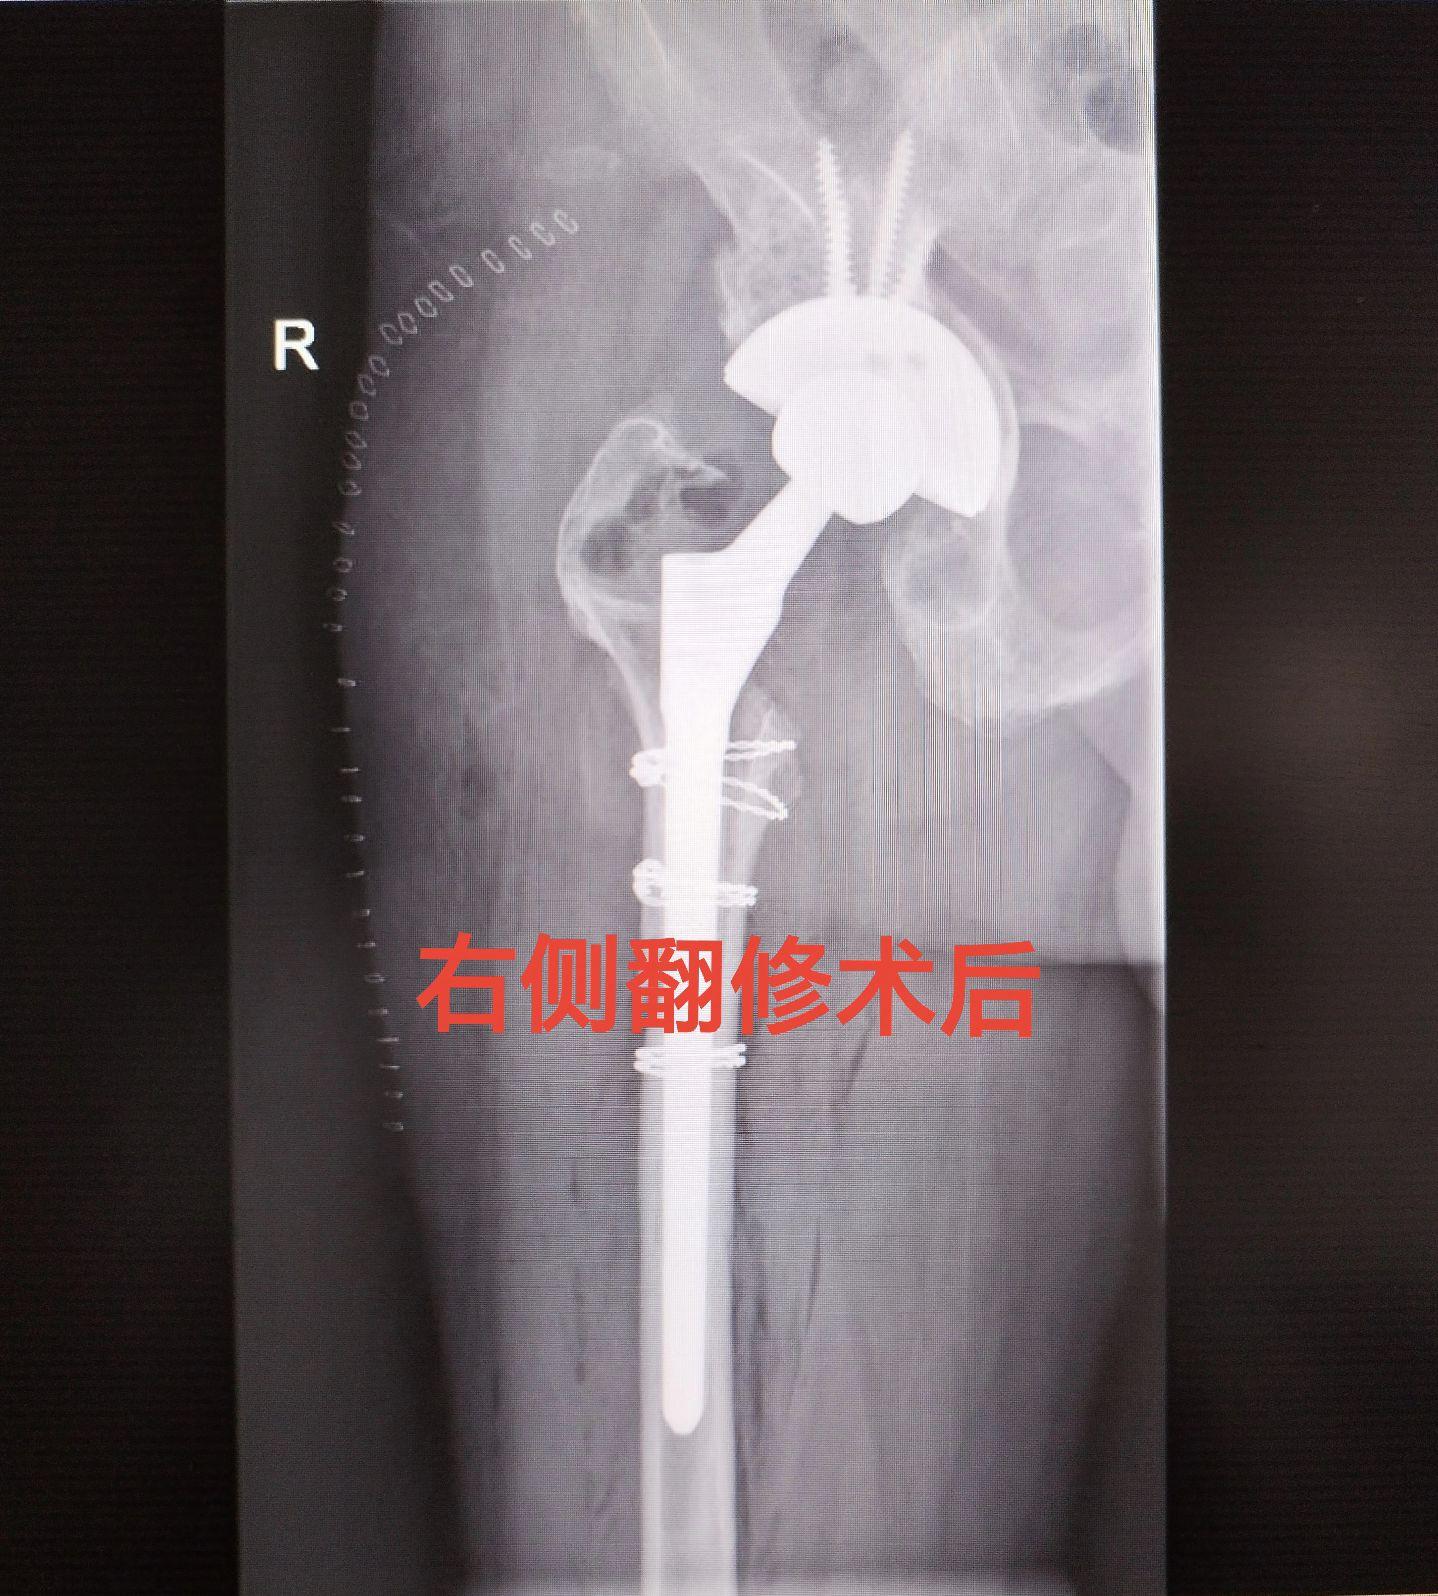

髋关节翻修术。髋关节置换术后假体磨损松动,双侧分次翻修。